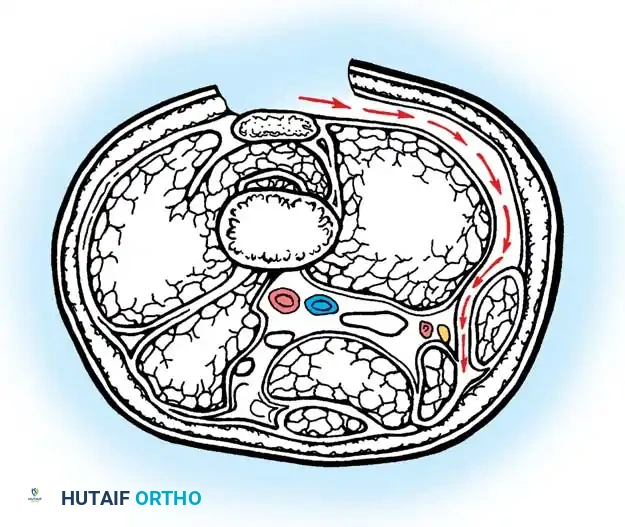

In CP, the hip and the knee are tightly coupled due to the complex network of "two-joint muscles" that cross both articulations. These crucial structures include the rectus femoris anteriorly, the gracilis medially, and the semimembranosus, semitendinosus, and biceps femoris posteriorly. Pathological conditions affecting these muscles—whether dynamic spasticity or fixed myostatic contracture—profoundly alter the kinematics of both joints. A similar interdependent relationship exists between the knee and the ankle via the gastrocnemius muscle.

Gastrocnemius Assessment

The degree of ankle equinus must be measured with the knee both flexed and fully extended (the Silfverskiöld test principle). If ankle dorsiflexion significantly improves when the knee is flexed, the gastrocnemius (a two-joint muscle) is the primary source of spasticity or contracture.

Fig. 30-22 Testing for gastrocnemius contracture and spasticity. A, With knee extended, equinus in ankle is noted. B, With knee flexed, ankle is easily dorsiflexed, indicating no soleus contracture. C, As knee is extended, ankle dorsiflexion is resisted by tight or spastic gastrocnemius muscles.

Lateral Hamstring Lengthening (If Indicated):

* If further correction is required to achieve full extension, proceed to the lateral side.

* Identify the biceps femoris tendon.

* Crucial Step: Meticulously isolate the biceps femoris from the common peroneal nerve, which lies immediately along its medial and posterior border.

* Pass a blunt right-angle instrument deep to the biceps femoris tendon to protect the nerve. Incise its tendinous portion transversely at two levels approximately 3 cm apart, leaving the muscle fibers intact.

Incisions in biceps femoris; note hemostat anterior to peroneal nerve protecting the neurovascular structures.